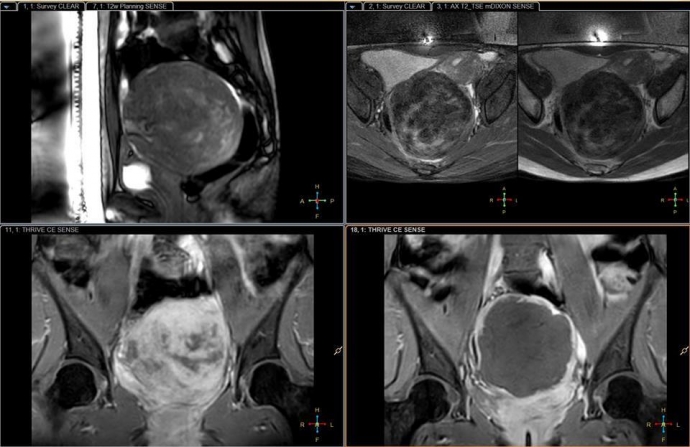

Hình ảnh khối u xơ choán hết phần tử cung, gây nên suy thận cho bệnh nhân |

Qua thăm khám, bác sĩ thông báo chị có một khối u xơ tử cung khoảng 100mm, chiếm toàn bộ tử cung và phần bụng dưới. Cũng qua kết quả chụp chiếu, khối u xơ tử cung chiếm hoàn toàn vùng chậu của chị H., đồng thời, nhận bệnh nhân đã bị thận ứ nước nặng độ 2 cả hai thận, suy giảm chức năng thận.